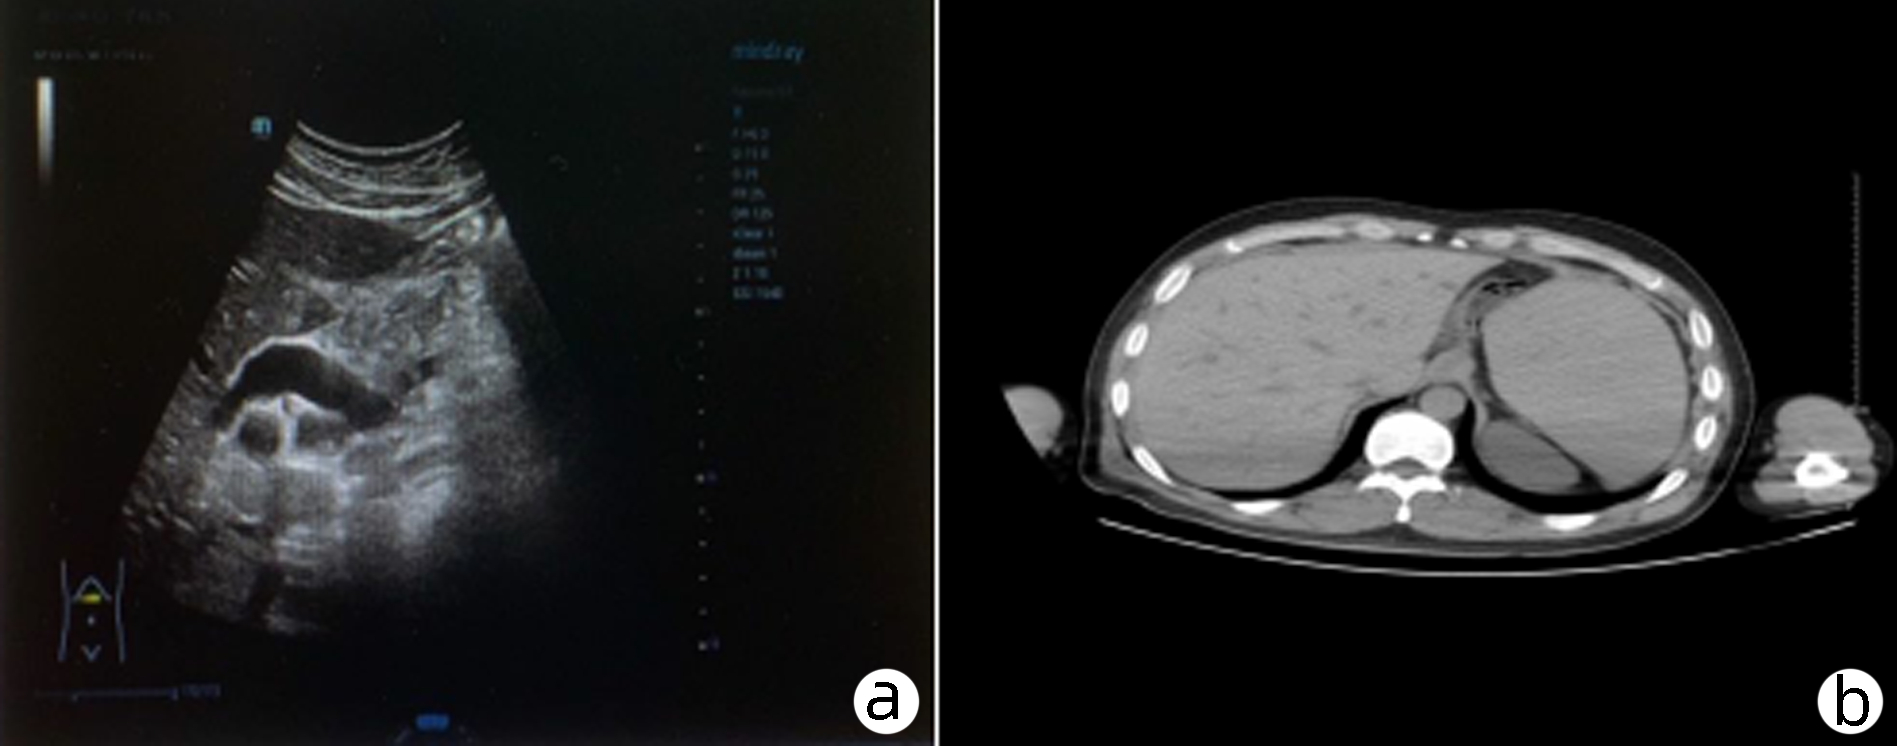

Sepsis with spontaneous splenic rupture and hemorrhage: A case report

Zhou LIU, Wenfang XIA, Liying ZHAN, Xiaoyu FANG, Liang ZHANG, Na ZHAN, Rong YU, Li HANG, Lei ZHU

2023, 39(8): 1926-1931. DOI: 10.3969/j.issn.1001-5256.2023.08.024

Abstract(1350) HTML (295) PDF (4249KB)(102)

Abstract:

Severe infections due to sepsis often result in multi-organ insufficiency, such as cardiac insufficiency, renal insufficiency, hypohepatia, septic encephalopathy, coagulation dysfunction etc. Severe infections not only cause inflammatory storm, but also induce spleen abscess, and even combined with spontaneous splenic rupture hemorrhage. Spontaneous splenic rupture has an insidious onset, usually without a history of trauma, and is easily missed diagnosis. In this case, the patient with sepsis had sudden onset of abdominal pain and progressive decrease in hematocrit, thus the abdominal CT was immediately performed. The perisplenic mixed high-density shadow indicated splenic hemorrhage. After consultation with the department of hepatobiliary surgery, emergency dissection was performed. Splenic hematoma and laceration were found during the operation, thus total splenectomy was conducted. Pathological indicated chronic inflammatory cell infiltration of spleen, spleen abscess with bleeding. After operation, the patient's hematocrit was stable, abdominal pain improved significantly, and he was discharged from hospital after systematic therapy.